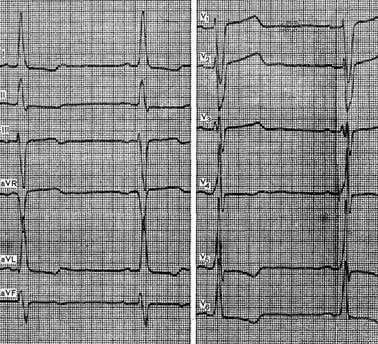

Типичные признаки выраженной гипертрофии левого желудочка с дистрофическими изменениями миокарда можно видеть на ЭКГ больного 63 лет с диагнозом: ревматический порок сердца, стеноз устья аорты. Отмечается отклонение электрической оси сердца влево до -15°, увеличение амплитуды зубца R в отведении V5 более 30 мм и зубца S в V1 более 25 мм. Зубец R в отведении V5 выше, чем в V4. Время внутреннего отклонения в левых грудных отведениях превышает 0,05 с. Отмечаются депрессия сегмента ST и инверсия зубца Т в отведениях I, aVL, V5 и V6, а также подъем сегмента ST в отведениях V1 и V2, Выявляются также признаки гипертрофии левого предсердия.